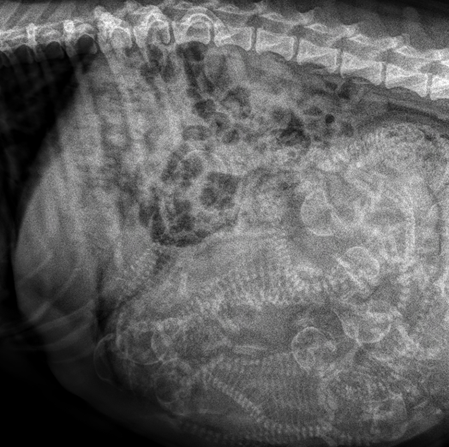

Rötngen